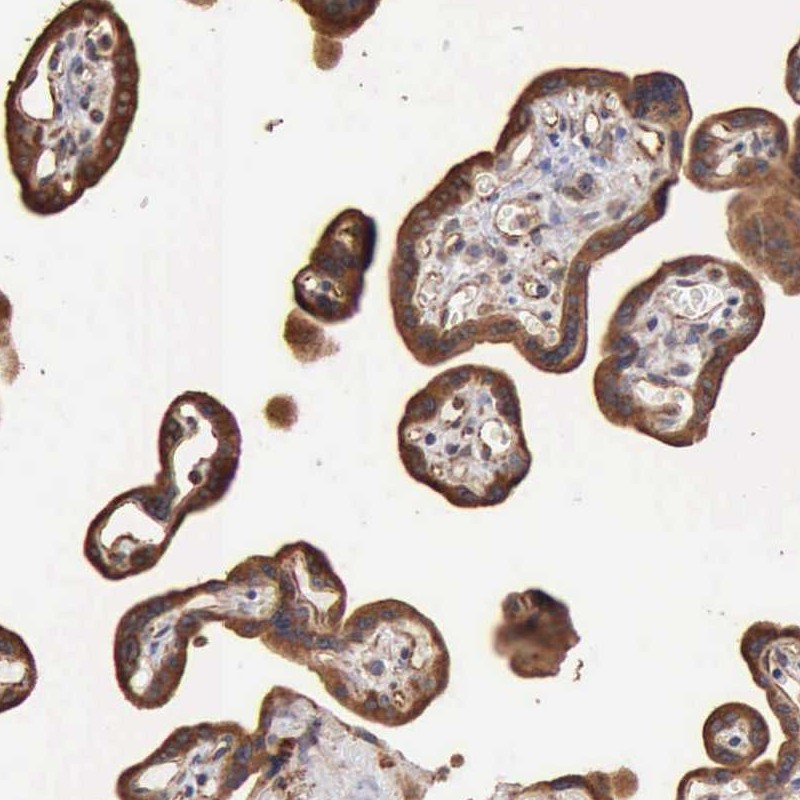

Immunohistochemical staining of human placenta shows strong membranous and cytoplasmic positivity in trophoblastic cells.